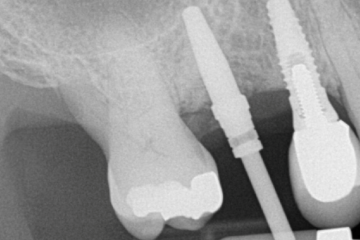

Η διαδικασία αυτή απαιτεί συνεργασία ανάμεσα στον περιοδοντολόγο και τον οδοντίατρο που θα κάνει την αποκατάσταση του εμφυτεύματος (θήκη, γεφυρα, οδοντοστοιχία). Μετά από επικοινωνία με τον οδοντίατρο και την ανάλυση τρισδιάστατης ακτινογραφίας αποφασίζεται η ακριβής θέση του εμφυτεύματος. Στη συνέχεια κατασκευάζεται χειρουργικός νάρθηκας ο οποίος χρησιμοποιείται ως οδηγός κατά την τοποθέτηση του εμφυτεύματος.

Είναι η τοποθέτηση εμφυτευμάτων με τη βοήθεια ηλεκτρονικού υπολογιστή η οποία προσφέρει μέγιστη ακρίβεια και προβλεψιμότητα στην τοποθέτηση του εμφυτεύματος. Μετά τη λήψη τρισδιάστατης ακτινογραφίας, το περιστατικό σχεδιάζεται με τη βοήθεια ηλεκτρονικού υπολογιστή όπου επιλέγεται η ιδανική θέση του εμφυτεύματος. Με βάση τη θέση αυτή κατασκευάζεται χειρουργικός νάρθηκας ο οποίος εφαρμόζει στα γειτονικά δόντια την ώρα της επέμβασης και καθοδηγεί την τοποθέτηση του εμφυτεύματος ώστε να γίνεται με μεγάλη ακρίβεια. Με τον τρόπο αυτό, σε αρκετές περιπτώσεις μειώνεται η ανάγκη για οστικό μόσχευμα πριν ή κατά την τοποθέτηση του εμφυτεύματος και συνεπώς η ταλαιπωρία του ασθενούς